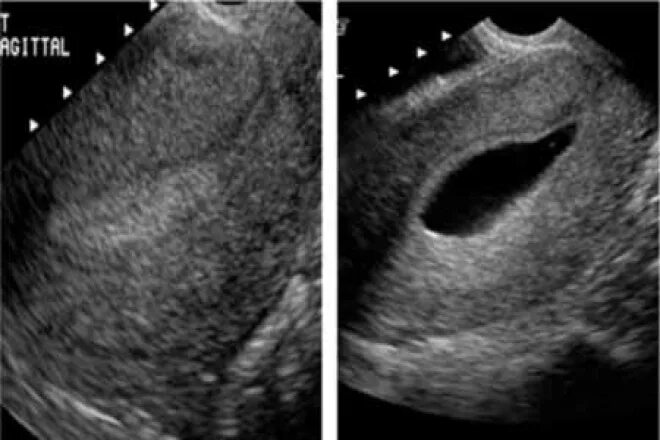

Гематометра симптомы